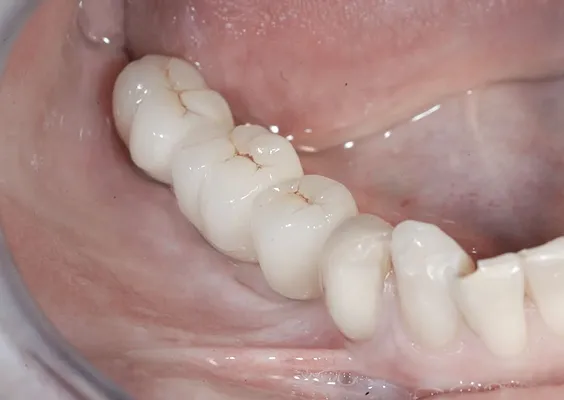

Zabieg odbudowy zębodołu powinno się wykonać możliwe jak najszybciej po usunięciu zęba. Jego celem jest odbudowa naturalnej objętości kości w miejscu utraconego zęba, a następnie szybkie wprowadzenie implantu. Najlepsze rezul-taty uzyskuje się przy zastosowaniu biomateriału w formie bloczków kolageno-wych lub granulatu, które dają trwałe efekty odbudowy oraz optymalną funkcję i estetykę odtworzonych koron zębów na wszczepionym implancie.

Przy zabiegu wszczepienia implantu nie zawsze niezbędna jest odbudowa kostna okolicy implantowanej. W sytuacji istnienia prawidłowej objętości kości we wszystkich wymiarach implantujemy bez odbudowy kostnej. Przy niedostatku kości w jednym z wymiarów warunkiem prawidłowego osadzenia i wgojenia implantu jest regeneracja kostna. Ma ona wpływ zarówno na względy biologiczne, czyli prawidłowe wgajanie się implantu, jak i względy funkcjonalne – brak retencji pokarmów pod prawidłowo uformowanymi koronami. Istotne dla pacjenta są również względy estetyczne, które osiąga się poprzez anatomiczne odtworzenie kształtu dziąsła rozpiętego nad odbudowaną kością, dające prawidłowe wyłonienie korony protetycznej odtwarzanego zęba. Uwzględnienie odtworzenia zarówno kości, dziąsła, jak i koron zębów daje w pełni estetyczne i funkcjonalne efekty, które najlepiej imitują własne uzębienie.